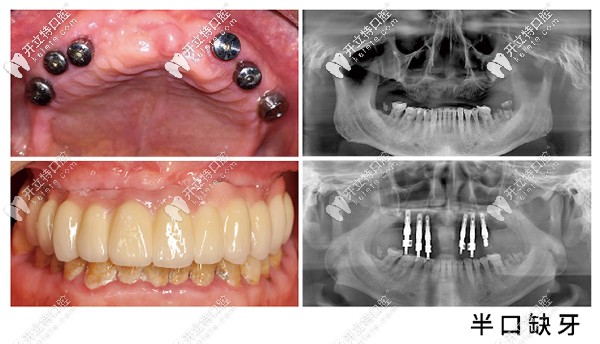

昆明美奧口腔半口種植牙案例

一般在昆明做半口種植牙價(jià)格在8萬以上,所以昆明美奧口腔收費(fèi)不算貴。咱們要知道種牙不僅要看價(jià)格,醫(yī)生技術(shù)也是考驗(yàn)后期使用長短的。